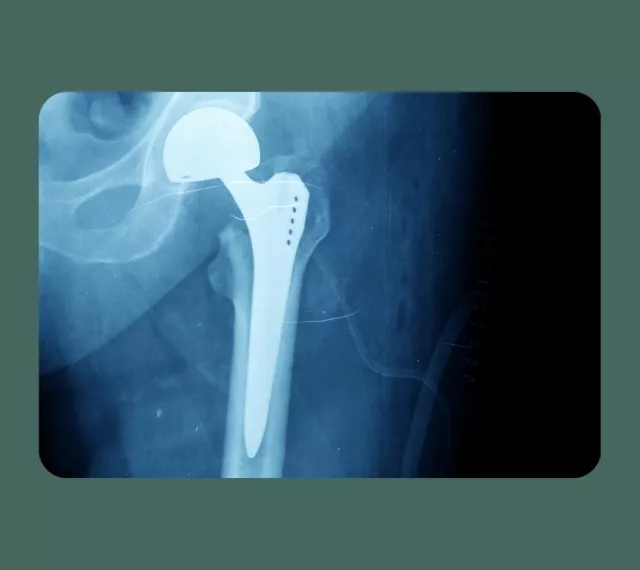

Wat hij het mooiste vindt aan zijn vak? De combinatie van denken en doen. “En vooral het resultaat. Patiënten met een nieuwe heup of knie merken vaak snel verschil. Ze kunnen weer beter bewegen en hebben minder pijn.”

Veel mensen denken dat orthopedisch chirurgen alleen heupen en knieën vervangen. Dat klopt niet. “We behandelen het hele bewegingsapparaat. Soms met een operatie, maar vaak ook zonder.”

Marc promoveerde in 2021 op onderzoek naar kwetsbare ouderen met een gebroken heup. Zijn onderzoek helpt artsen en patiënten om samen de juiste keuze te maken voor behandeling, met aandacht voor kwaliteit van leven en psychisch welzijn. Bekijk zijn onderzoek hier